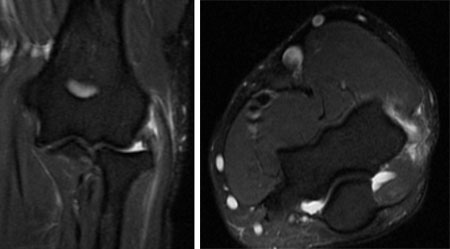

Coronal MRI and axial MRI in the same patient, showing high signal in extensor carpi radialis brevis

From the collection of Daniel J. Solomon, Naval Medical Center San Diego, CA; used with permission